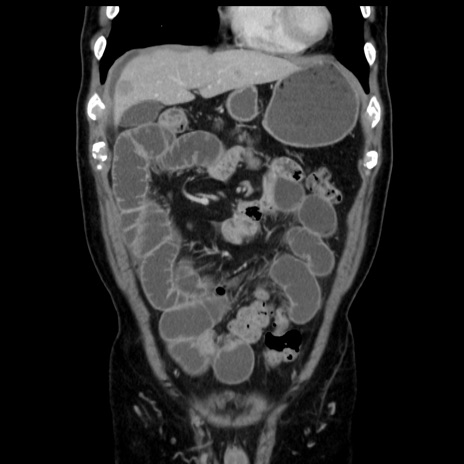

症例16(冠状断像)

【症例】 70歳代男性

【主訴】 腹痛、嘔吐

【現病歴】 約1ヶ月前より間欠的に腹痛と嘔吐あり、当院消化器内科を受診したところCTで多発する肝臓のLDAを指摘され、精査中であった。以降は消化器症状は安定していたが、2日前より嘔気と腹痛があり、同日より排便・排ガスが消失した。改善認めず、 本日、救急外来を受診した。

【既往歴】 大腸ポリープ切除後。

【身体所見】意識清明・会話良好、BT 36.3℃、BP 127/80mmHg、 P 80bpm、腹部:膨満あり、平坦・軟、上腹部正中および下腹部正中に圧痛あり、反跳痛なし、筋性防御なし。

【データ】WBC 7200、CRP 0.77